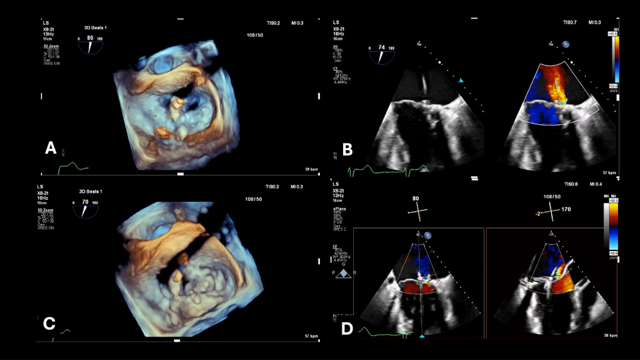

Intraprocedural TEE confirmed the pathology and, after appropriate transeptal puncture, a MitraClip NT device (Abbott) was delivered to the left atrium and oriented perpendicular to the leaflet coaptation plane, just lateral to the Alfieri stitch at the location of the jet (Figure 4). The clip was closed and advanced into the left ventricle and the leaflets were grasped. Because of the baseline distortion of the leaflet anatomy from the stitch, clipping of the leaflets caused further distortion and an increase in MR. The clip was readjusted to a more lateral position, slightly farther away from the stitch, which resulted in significant MR reduction and minimal change in gradient, and the clip was released (Figures 4 and 5).